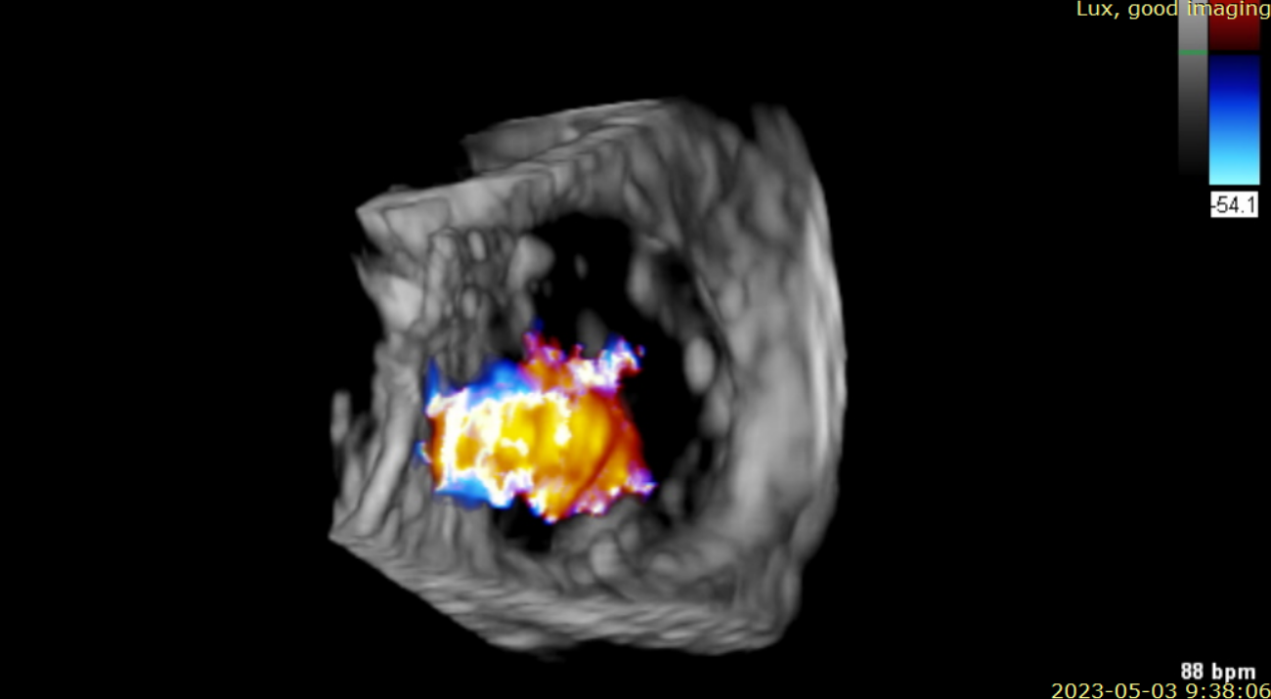

術(shù)后超聲提示無(wú)瓣周漏

術(shù)后超聲提示僅殘余輕微瓣周漏

術(shù)后Azeem Latib教授對(duì)LuX-Valve Plus經(jīng)血管三尖瓣置換系統(tǒng)的器械性能和治療效果大為稱贊,并且認(rèn)為L(zhǎng)uX-Valve Plus的手術(shù)體驗(yàn)非常好。從治療效果來(lái)看,術(shù)后即刻超聲顯示三尖瓣反流幾乎完全消失,血流動(dòng)力學(xué)改善顯著,患者恢復(fù)快。在面對(duì)復(fù)雜解剖結(jié)構(gòu)、超聲影像質(zhì)量不佳、有起搏導(dǎo)線干擾時(shí),Lux-Valve Plus也體現(xiàn)了極強(qiáng)的適應(yīng)性。Thomas Modine教授參與了術(shù)中指導(dǎo),他同樣再次肯定了LuX-Valve Plus術(shù)中操作的便捷性,認(rèn)為L(zhǎng)uX-Valve Plus容錯(cuò)率高,對(duì)術(shù)中影像的依賴小,并表達(dá)了后期希望可以更多地應(yīng)用LuX-Valve Plus三尖瓣置換系統(tǒng)于臨床實(shí)踐,讓更多的三尖瓣重度反流患者盡早獲益,改善預(yù)后。